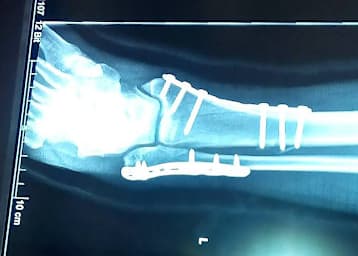

Der Knöchelbruch von Manfred Wechselberger wurde in Frankreich optimal versorgt